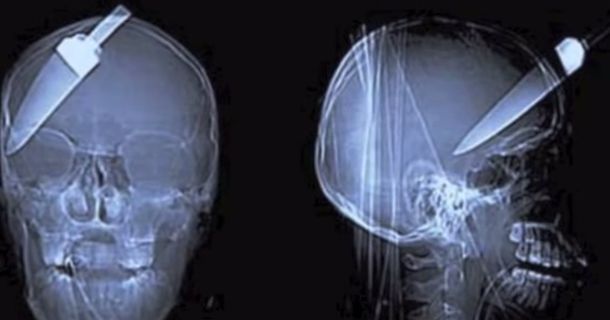

Wounds